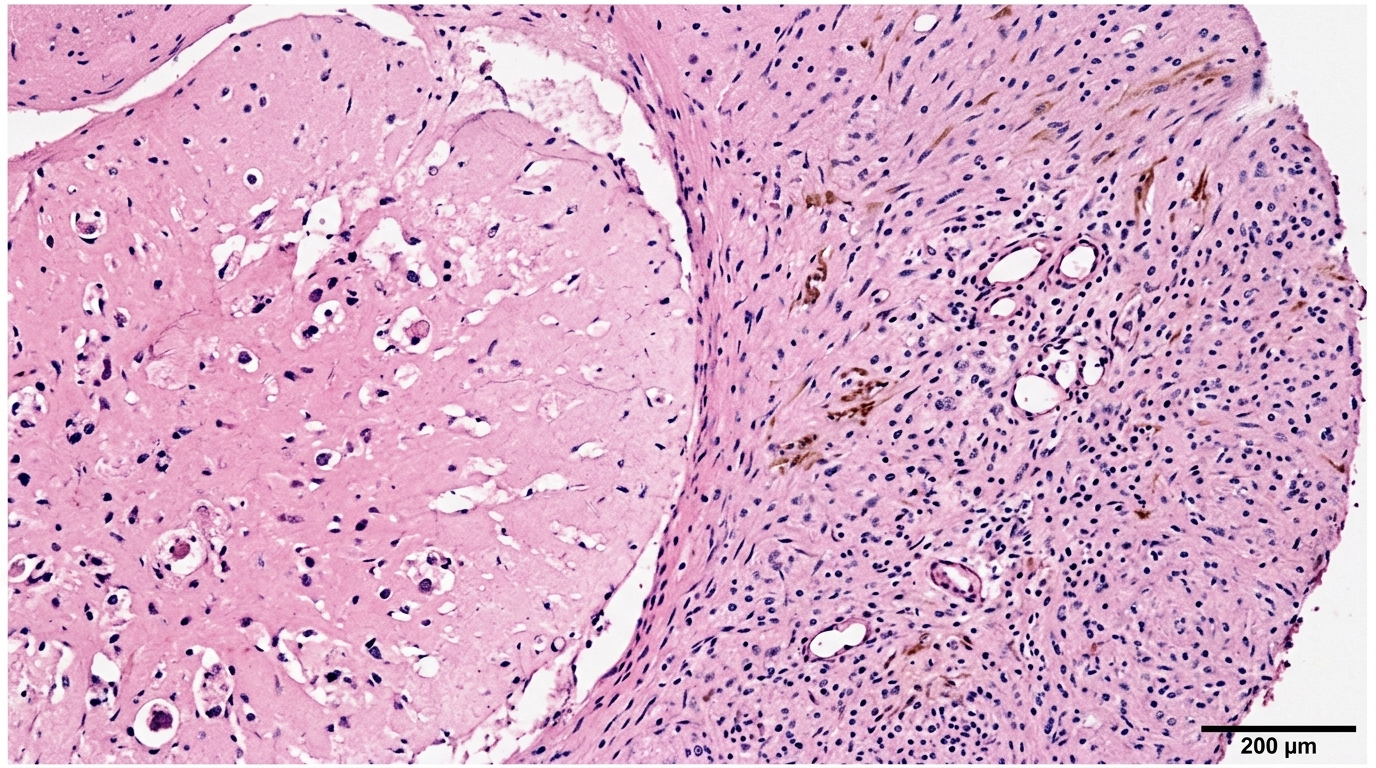

間質幹細胞分化

臍帶間質幹細胞來源於臍帶組織中的瓦頓氏膠(Wharton's Jelly),屬於多功能間質幹細胞。具備強大的自我更新與多向分化能力,可分化為骨細胞(Osteocytes)、軟骨細胞(Chondrocytes)及脂肪細胞(Adipocytes)。

臍帶間質幹細胞具多功能性,可分化為骨細胞、軟骨細胞及脂肪細胞,表達低量 MHC 分子,具備低免疫原性及抗發炎特性,適用於異體移植與組織修復研究。